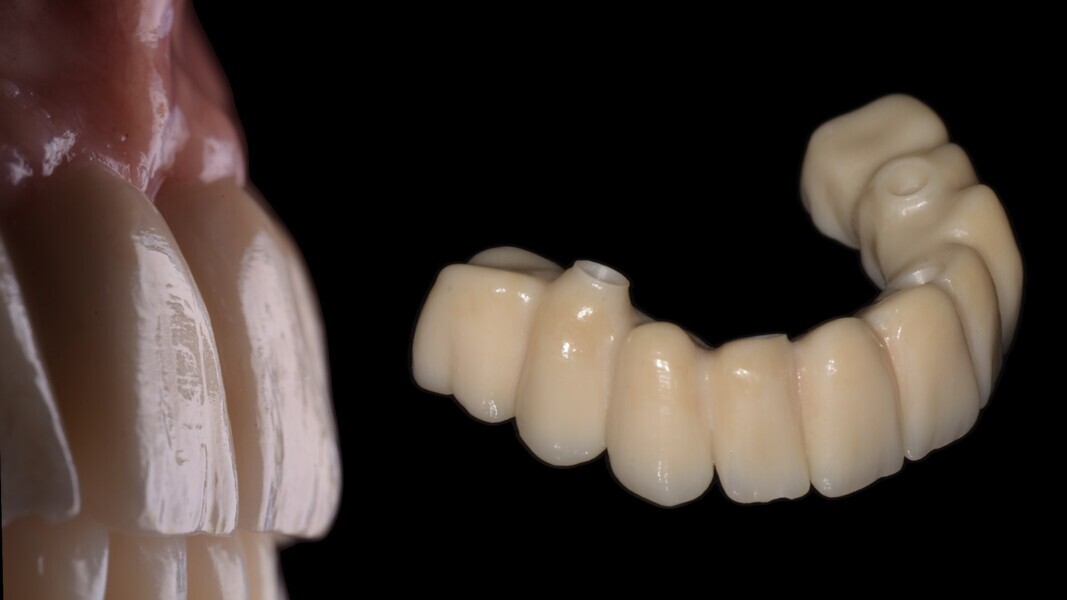

La réalisation d’un bridge transvissé usiné en PMMA avec vario-bases pour piliers multi-unit (Fig. 11) est usinée après l’utilisation de la caméra iTero pour l’empreinte des scan bodies au maxillaire.

Pour ce faire nous enregistrons la position des quatre scan bodies au maxillaire en postopératoire et le laboratoire superposera ce fichier STL, aux fichiers STL enregistrés initialement du maxillaire en occlusion avec la mandibule, ceci dans le but de mettre l’empreinte postopératoire avec scan bodies en occlusion avec le modèle mandibulaire, qui a déjà reçu un bridge provisoire transvissé quelques semaines auparavant.